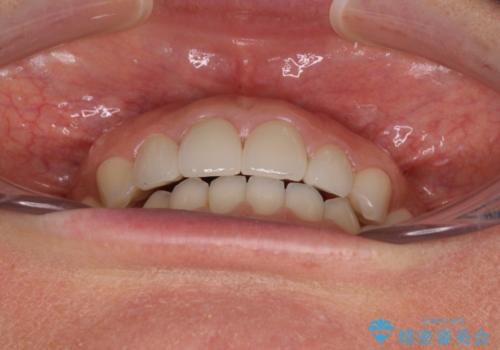

前歯を綺麗にしたい 部分矯正とセラミック治療

- 大きすぎる上顎前歯と、隙間の空いた下顎歯列を気にして来院された患者様です。

上顎前歯にはセラミッククラウンが装着されており、顔や他の歯と比較して幅の大きい状態でした。

下顎前歯は空隙歯列弓であったので、アンカースクリューとワイヤー装置を用いてスペースを閉じていくこととし、上顎前歯は矯正治療用の仮歯に置き換えた上で、仮歯の大きさを削って小さくしながら、上下前歯部の部分矯正を行うこととしました。

矯正治療後は、仮歯とした上顎前歯をオールセラミッククラウンにて補綴治療を行うこととしました。